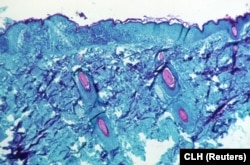

Оспа обезьян – инфекционное вирусное заболевание, которое вызывает вирус семейства поксовирусов, близкий к вирусу натуральной оспы. Однако, в отличие от натуральной оспы, которая только за ХХ век унесла жизни сотен миллионов человек, оспа обезьян в основном заражает животных, редко передается от них человеку и намного менее опасна (летальность – не более 11 процентов, тогда как у натуральной оспы она доходила до 40 процентов, а в некоторых эпидемиях и до 90 процентов).

Симптомы оспы обезьян у людей – лихорадка, головные и мышечные боли, обильное потоотделение, а также типичная сыпь, после которой могут остаться постоянные рубцы. Как правило, болезнь проходит сама в течение 2–4 недель после появления первых симптомов (инкубационный период длится от недели до 19 дней).

Передача вируса происходит через биологические жидкости, в первую очередь – через содержимое появляющихся на теле везикул, проникающее в организм другого человека через повреждения на коже и слизистые оболочки, и требует продолжительного и тесного контакта. Есть данные о передаче воздушно-капельным путем, но, вероятно, этот путь является второстепенным. Необходимость продолжительного тесного контакта, а также тот факт, что больной становится способным к заражению после появления очевидных симптомов (высыпаний), сдерживают распространение обезьяньей оспы.

Наиболее вероятное объяснение – человечество постепенно теряет иммунитет к натуральной оспе, полученный как переболевшими, так и в ходе массовой вакцинации. Натуральная оспа была полностью элиминирована к 1980 году (образцы вируса хранятся сейчас только в двух лабораториях в мире, в России и США), и вакцинация была остановлена, с тех пор коллективный иммунитет к ней постепенно ослабевает. Вирус оспы обезьян генетически близок к вирусу натуральной оспы и постепенно получает все больше возможностей для распространения в человеческой популяции.